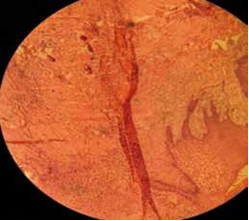

33. No discharge on palpation from growth was seen. Calculus was present between 31, 32, 33 teeth. On the basis of history & clinical examination, a provisional diagnosis gingival epulis was made. The differential diagnosis considered was traumatic firoma, pyogenic granuloma, Peripheral fibroma with calcification, Peripheral Cemento-ossifying fibroma, and Peripheral giant cell granuloma. The intraoral periapical radiograph 31, 32, 33, 41 and orthopantomographic (OPG) examination showed no obvious bony changes. (Figure 2 a & b). All the hematological reports were in normal limits. Later with patient consent, excision of the lesion was done under local anesthesia (Figure 3) and the specimen was sent for histopathological examination, which showed parakeratinzed stratified squamous epithelium of variable thickness with evidence of ulceration in some areas. The underlying dense fibrous connective tissue shows varying degrees of cellularity along with foci of mineralization. The hard tissue component showed basophillic acellular spherules. There was presence of focal chronic inflammatory cell infiltrate and granulation tissue formation in some areas. These features were suggestive of peripheral cemento-ossifying fibroma. (Figure 4) In the present case, after excision of the lesion, all the remnant of the lesion was removed and thorough debridement was done. Capsule amoxicillin (500mg), tablet metronidazole (400mg) and tablet ibuprofen (400mg) were prescribed to the patient thrice daily for five day postoperatively, to relieve the pain and to prevent secondary infection Following this, close monitoring was done after 10 days, 1 month, 3 months and 6 months and no recurrence was observed. The surgical site appeared to be healing well. The patient was asymptomatic, aesthetically sound and satisfied with results on follow up.

Radiographically, PCOF may follow different patterns depending on the amount of mineralized tissue, radio-opaque foci of calcification have been reported to be scattered through the central area of the lesion, but not all lesions exhibit these radiographic characteristics. Most lesions are not associated with bone destruction. In rare instances, superficial erosion of bone is noted (5,8). Radiographic finding were non-contributory in the present case. Histologically, the lesion appears as non- encapsulated fibrous connective tissue with parakeratinzed stratified squamous epithelium of variable thickness with evidence of ulceration in some areas. Benign fibrous connective tissue with varying content of fibroblasts, myofibroblasts and collagen, sparse to profuse endothelial proliferation, mineralized material which may represent mature, lamellar or woven osteoid, cementum like material or dystrophic calcifications. Acute or chronic inflammation related findings can also be identified in lesions (5). Most of these features were reported in present case. This emphasizes the need for histopathological examination of biopsy specimen for an accurate diagnosis because of difficulty in diagnosing PCOF based only on clinical and radiographical observation.